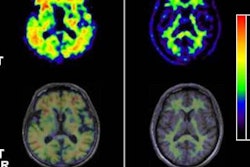

The tracer is used for PET imaging to evaluate patients suspected of having Alzheimer's disease and other forms of cognitive impairment, according to Piramal.